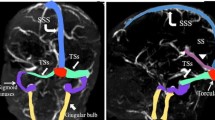

Cerebral sinovenous thrombosis (CSVT) is defined by thrombosis within the superficial (cortical veins, superior sagittal sinus, transverse sinus, sigmoid sinus, and jugular vein) or deep (inferior sagittal sinus, internal cerebral veins, vein of Galen, straight sinus) venous system [1]. Although likely underestimated, CSVT occurs in about one of 100,000 children per year including neonates and accounts for one in four cases of pediatric stroke [2]. CSVT is associated with high mortality and morbidity. Pediatric CSVT cohort studies report mortality rates of 8–19 % and severe long-term neurological sequelae in 38–48 % of patients [2, 3]. Acute antithrombotic interventions to prevent thrombus propagation are increasingly used in children and are expected to decrease the mortality and improve the long-term outcome [4]. However, the diagnosis of CSVT must first be made as soon as possible after onset of symptoms.

In 33 children, we found a total of 77 thrombi. Multiple thrombi have been found in 24 patients (73 %) including five thrombi in one child, four thrombi in three children, three thrombi in nine children, and two thrombi in 11 children. In nine patients (27 %), only one thrombus was present. Thrombi have been seen at different locations within the superficial and/or deep venous system. The majority of thrombi (90 %) was found in the superficial venous system (Table 3). The transverse (34 %) and sigmoid (24 %) sinuses were the most common locations of thrombi.

Patent venous sinuses usually have low signal intensity due to flow-related signal void on spin-echo images and are best seen on T2-weighted and FLAIR images. On spin-echo images, thrombosis causes time-dependent changes of signal intensity within the affected sinuses [6, 7]. The signal intensity varies during thrombus evolution and depends on the interval between the onset of thrombus formation and the time of imaging [8, 9]. Changes in signal intensity over time are related to the paramagnetic effects of the products of hemoglobin breakdown in the thrombus and parallels extravascular clot evolution [7, 8, 10–12]. Thrombus evolution has been classified into four different stages: (1) hyperacute thrombosis (<24 h), (2) acute thrombosis (1 to 3 days), (3) subacute thrombosis (early subacute: 3 to 7 days and late subacute: 7 to 14 days), and (4) chronic thrombosis (>14 days) [2]. Previous neuroimaging literature showed that the hyperacute thrombus has an isointense signal on T1-weighted images due to lack of flow-related signal void and a slightly hyperintense signal on T2- and FLAIR images due to residual intracellular oxyhemoglobin. In the acute stage, the thrombus may appear predominantly T1-isointense and T2- and FLAIR-hypointense due to lack of flow-related signal void and the presence of intracellular deoxyhemoglobin, respectively. During the early subacute stage, intracellular methemoglobin causes the thrombus to appear T1-hyperintense and T2- and FLAIR-hypointense. In the late subacute stage, the thrombus remains T1-hyperintense, but the accumulation of extracellular methemoglobin leads to a hyperintense signal on T2-weighted and FLAIR images. Finally, the chronic thrombus has a hypointense signal on T1-weighted, T2-weighted, and FLAIR images due to hemosiderin [2, 7, 9, 11, 13, 14]. The changes in signal intensity of the thrombus over time have been used to estimate its age [2, 7, 9, 11, 13, 14].

In our study, the signal intensity of the thrombus was highly variable on the spin-echo images. We found T1-isointensity and T1-hypointensity of the thrombus in the hyperacute and early subacute phase (Fig. 1). Iso- and hypointense signals of the thrombus on T2-weighted and FLAIR images were seen in hyperacute and acute as well as early subacute stages (Fig. 2). Finally, T1-, T2-, and FLAIR-hyperintense signal was seen at all the different stages of thrombus evolution (Fig. 3). Statistical analysis showed a significant correlation only between T1-signal intensity and age of the thrombus: T1-hyperintense thrombi were more likely to be older than 1 day. No correlation was found between age of the thrombus and signal intensity on T2-weighted and FLAIR images. Our results are not matching the previous literature. Two possible explanations are the following: (1) the duration of each stage of thrombus evolution is only approximate and factors such as variability in the degree of initial oxygenation of the red blood cells in the developing thrombus and dilution may affect the rate at which the thrombus evolves and (2) secondary extension of the thrombus may lead to different ages of thrombus evolution resulting in non-uniform signal intensities [2, 8]. In addition, the retrospective design of our study did not always allow a precise estimation of the age of the thrombus. Our study, however, matches the clinical pediatric neuroradiology daily practice and shows the difficulties in approximating the age of the thrombi.